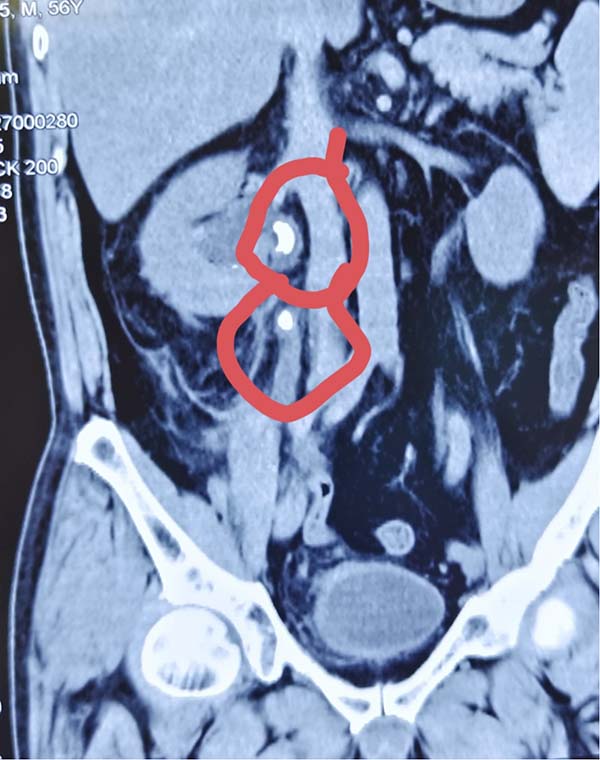

据悉,该患者因腰部剧烈疼痛并伴有血尿症状来院就诊。经检查,发现其输尿管上段嵌顿着2颗较大结石,下段1块结石。若采用传统单一的手术方式,往往需要分次进行,一次经尿道输尿管硬镜激光碎石术,一次经皮肾镜激光碎石术,不仅增加患者痛苦和经济负担,也延长了治疗周期。

手术当日,在于春虎主任的精准操作下,团队首先利用输尿管硬镜经尿道进入,顺利处理了位于输尿管下段的结石。随后,在硬镜建立的通道基础上,将纤细灵活的输尿管软镜送达位置更深、角度更刁钻的输尿管上段。软镜前端可弯曲的特性,使得医生能够无死角地观察结石情况,并利用先进的激光碎石设备将结石精准粉末化。最终,手术团队成功将输尿管上段和下段两处的结石一次性彻底清除。整个手术过程流畅,最大限度地减少了对患者正常组织的损伤。目前,该患者恢复良好,对手术效果非常满意,已经康复出院。